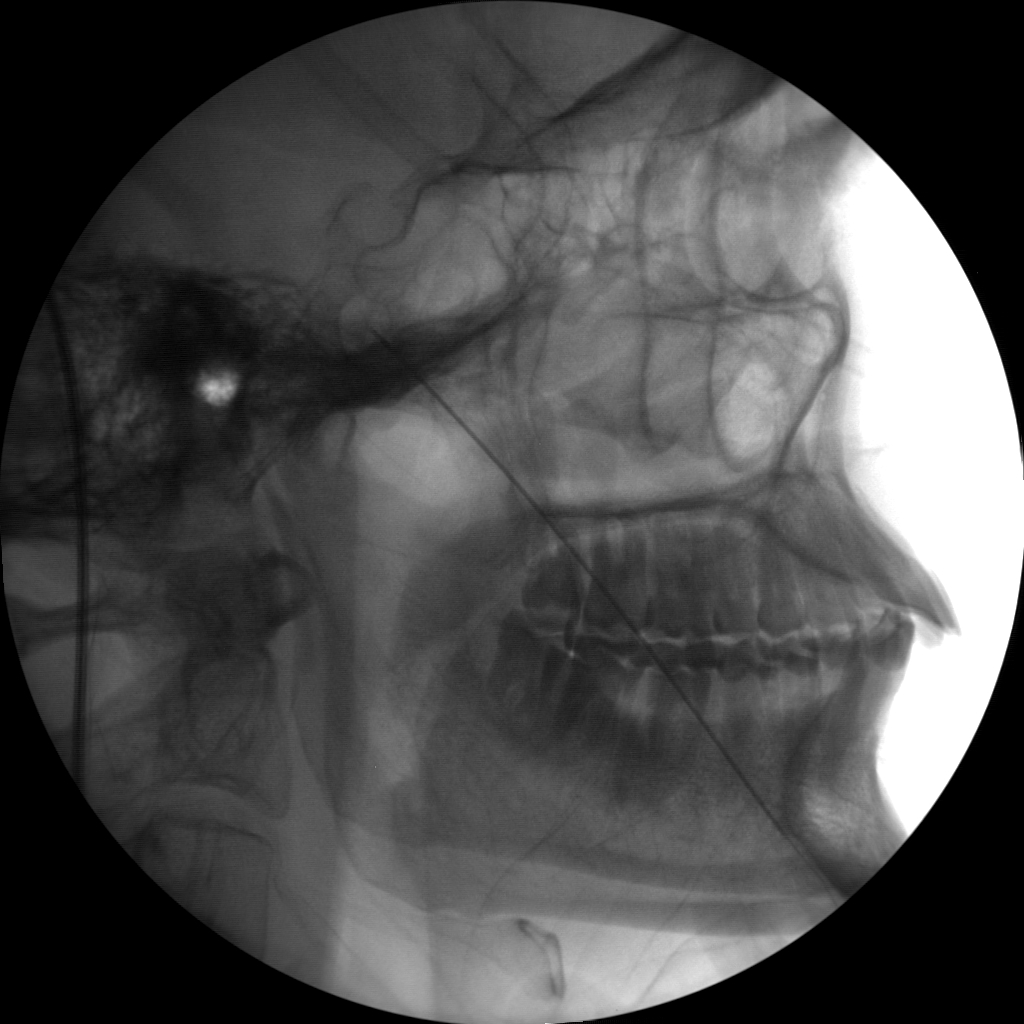

Radio frequency Ablation (RFA)

Skan-C is an invaluable tool for performing Radiofrequency Ablation (RFA), a procedure that uses heat to disable nerves responsible for transmitting pain signals. Skan-C's advanced imaging capabilities facilitate precise localization of the target nerves, guiding the placement of the RFA needle electrode accurately.